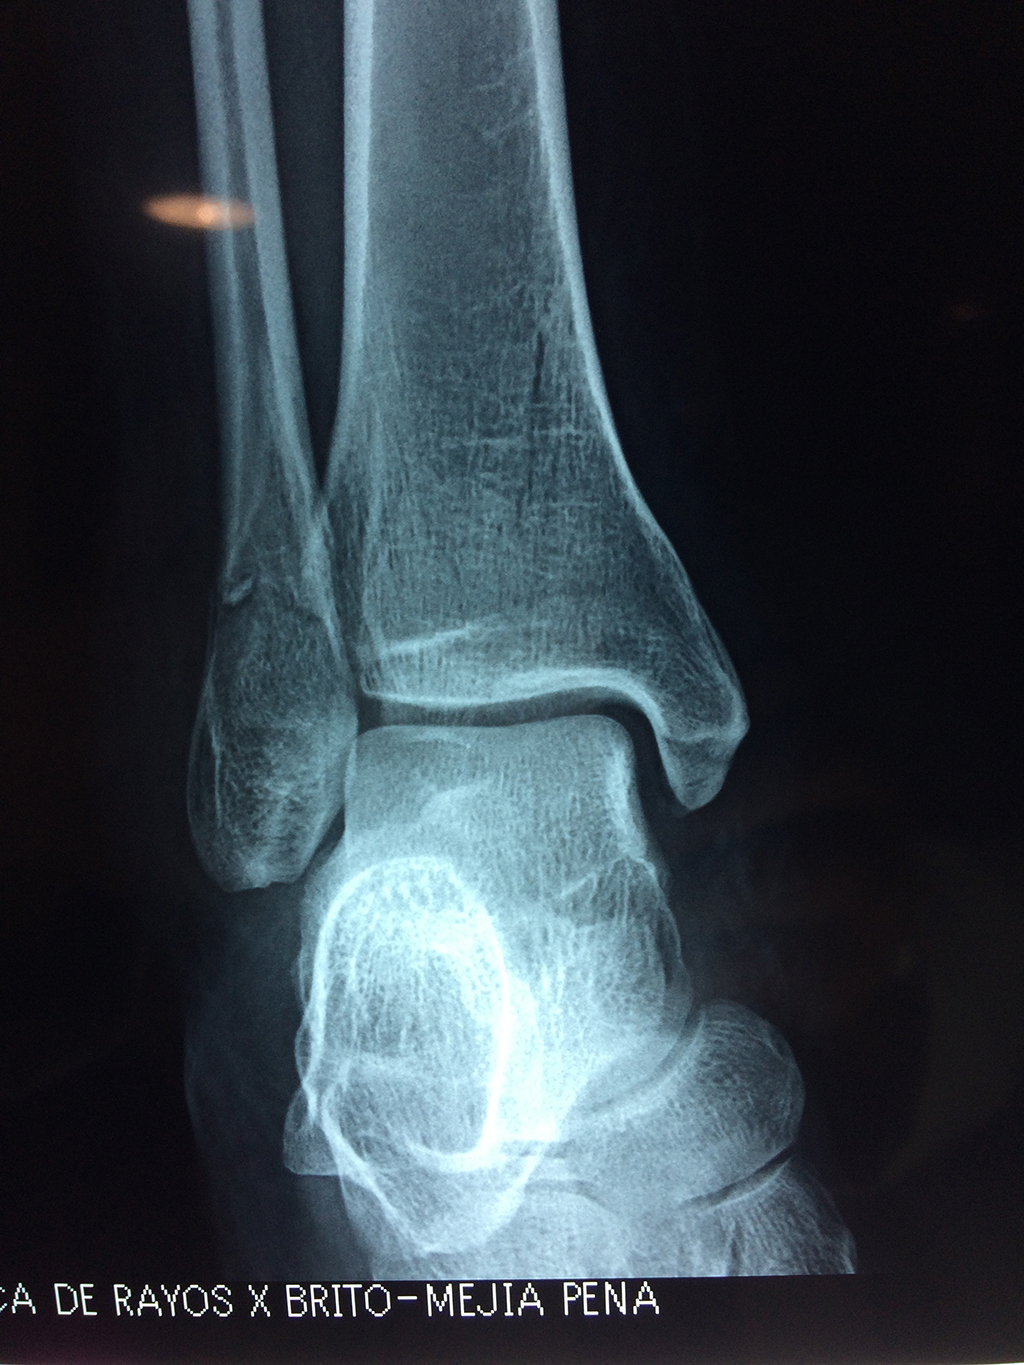

Algunas fracturas de tobillo pueden requerir cirugía si:

- Los extremos de los huesos están desalineados entre sí (desplazados).

- La fractura se extiende hasta la articulación del tobillo (fractura intra-articular).

- Los tendones o ligamentos (tejidos que sujetan los músculos y los huesos entre sí) están rotos.